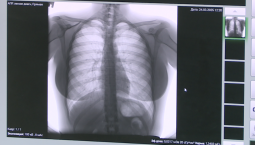

Напомним, врач-онколог назвал признак предракового состояния и раскрыл способы борьбы с ним. Распознать наличие развивающегося онкологического заболевания можно по частому покашливанию. Об этом заявил хирург и онколог Иван Карасев в соцсети.  По его словам, частое покашливание говорит о высокой вероятность появления полипов. Полипы - это новообразования, возникающие на слизистой оболочке гортани или голосовых связках.